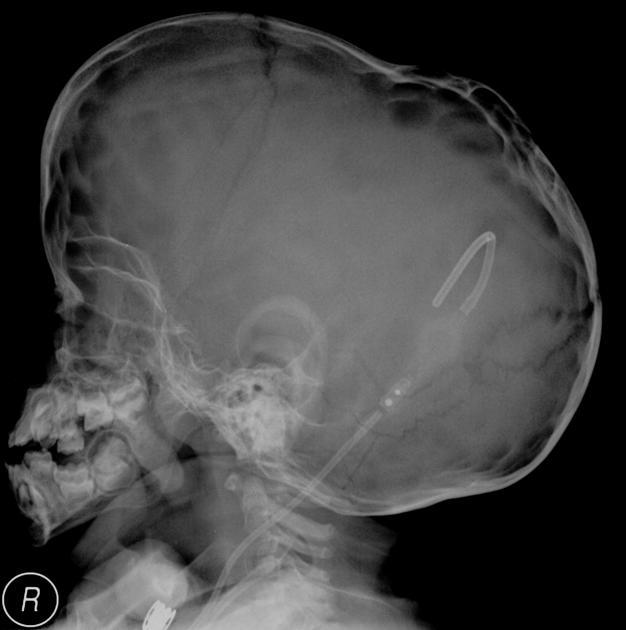

Luckenschadel

A

Lacunar skull or craniolacunae, is a dysplasia of the membranous skull vault and is associated with Chiari II malformations (seen in up to 80% of such cases). The inner table is more affected than the outer, with regions of apparent thinning (corresponding to unossified fibrous bone) of the skull vault. If particularly severe, with the individual lacunae coalescing into larger defects the term craniofenestrae is used.

Typically resolves after 6 months of age.